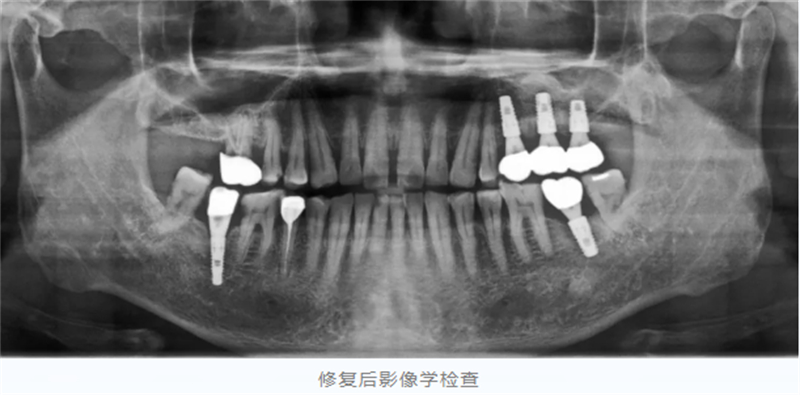

然而,经过详细影像检查,医生发现他左侧上颌后牙区牙槽骨严重吸收,骨高度仅存约2毫米,这为种植手术带来了很大挑战。

手术成功将骨高度从原来的约2毫米提升至10-12毫米,为种植体的植入奠定了更扎实的基础。